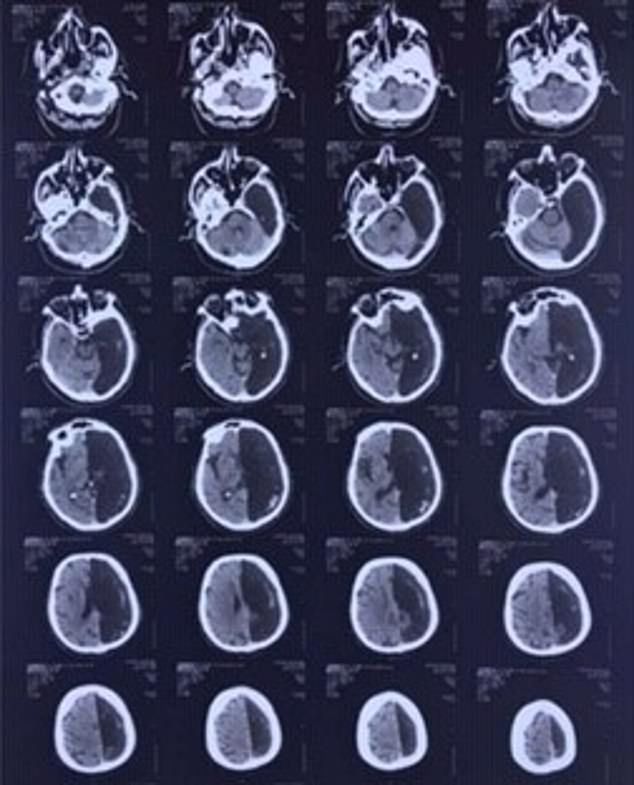

Rosjanin został przyjęty do szpitala po udarze. Miał problem z poruszaniem jedną ręką i nogą. Lekarze wykonali badania tomografem. Byli w szoku, gdy zobaczyli, że mężczyzna nie ma lewej części mózgu. To był pierwszy taki przypadek, z którym się spotkali. Pacjent nie był świadomy tego, że żyje tylko z połową mózgu.